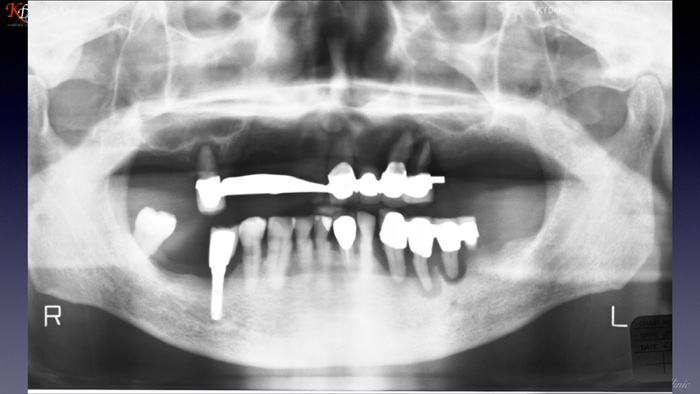

咬合再建・咬合回復shapeimage_22_link_0

症例に応じた治療手法の選択と咀嚼機能再現の効果http://www.kura-dent.com/Treatment%20and%20effects.pdfshapeimage_23_link_0